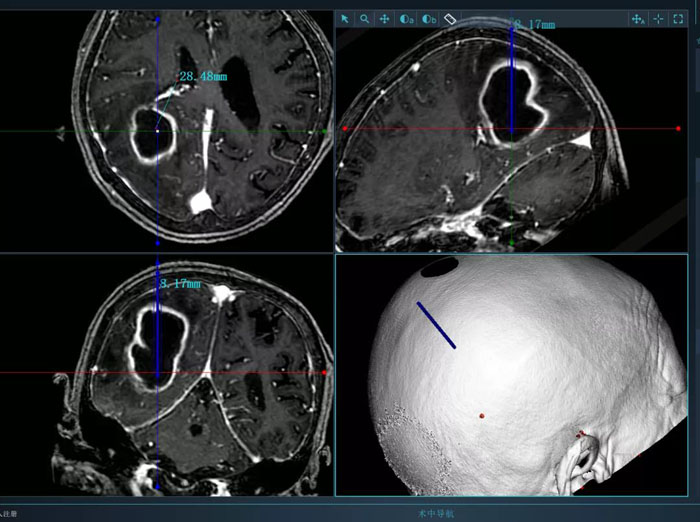

病例2.患者為74歲老年女性,術前因高熱入院,檢查發(fā)現(xiàn)腦膿腫。該患者體質較差,而且膿腫體積大,形態(tài)不規(guī)則,傳統(tǒng)穿刺引流方式難以完全將膿腫引流徹底,且易造成膿腫擴散,引起嚴重不良后果。續(xù)繼軍主任決定采用智能機器人輔助穿刺,術前借助智能機器人手術計劃系統(tǒng)避開腦重要功能區(qū)及血管,精心設計了最優(yōu)穿刺路徑。續(xù)繼軍主任帶領丁鵬主治醫(yī)師在機器人引導下行膿腫穿刺引流,一次穿刺到位,術中引流出腦膿腫25ml。術后,復查CT顯示引流管到達預定靶點,位置良好,膿腫引流滿意,患者顱高壓癥狀明顯緩解,腦膿腫得到有效控制。